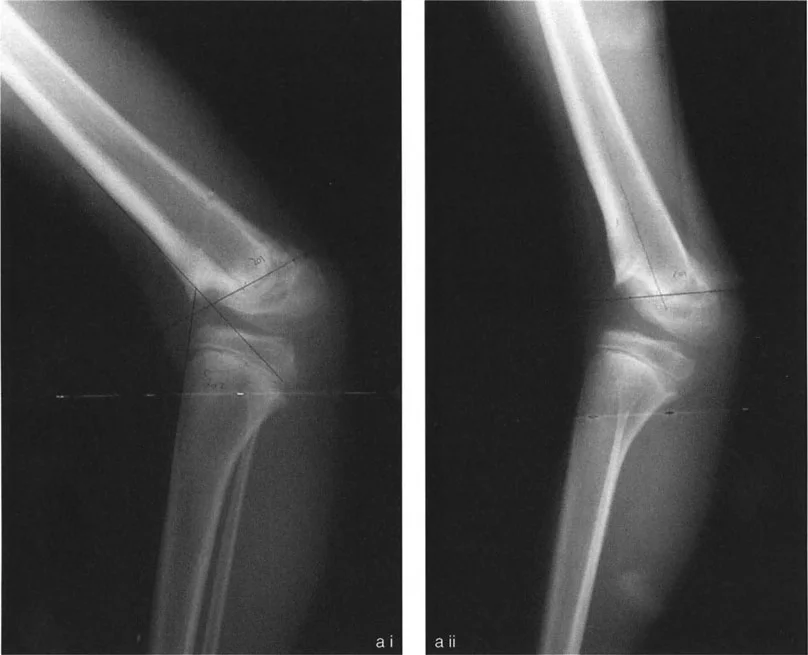

قبل أن يلمس المشرط أو منشار العظم العظم، يجب على الجراح تحليل التشوه بدقة باستخدام صور الأشعة السينية الكاملة للطرف مع تحمل الوزن. تعتمد مرحلة التخطيط على مبادئ هندسية صارمة تحدد مكان قطع العظم وكيفية إعادة محاذاته. هذا التخطيط الدقيق هو أساس نجاح عملية تصحيح تشوهات العظام.

المحور الميكانيكي للطرف والانحرافات

يُعرف المحور الميكانيكي للطرف السفلي بأنه خط وهمي يمتد من مركز رأس عظم الفخذ إلى مركز مفصل الكاحل. في الطرف الطبيعي، يمر هذا الخط قليلاً إلى الجانب الإنسي لمركز مفصل الركبة (حوالي 8 مم إنسيًا). يحدث انحراف المحور الميكانيكي عندما يقع هذا الخط خارج المعايير الطبيعية، مما يؤدي إلى توزيع غير طبيعي للضغط عبر مفصل الركبة. يُعد تصحيح هذا الانحراف الهدف الوظيفي الأساسي لجراحة إعادة محاذاة الطرف السفلي.

الأشعة السينية المحورية وتصوير الأطراف

يبدأ التخطيط بإجراء مجموعة شاملة من صور الأشعة السينية المحورية للطرف بالكامل أثناء تحمل الوزن. تسمح هذه الصور بتقييم دقيق للمحور الميكانيكي للطرف، وتحديد مدى الانحرافات الزاوية، وتحديد موقع مركز دوران الزاوية (CORA) بدقة متناهية. قد يتم أيضًا استخدام التصوير المقطعي المحوسب (CT) أو الرنين المغناطيسي (MRI) لتقييم الأنسجة الرخوة أو التشوهات المعقدة ثلاثية الأبعاد.